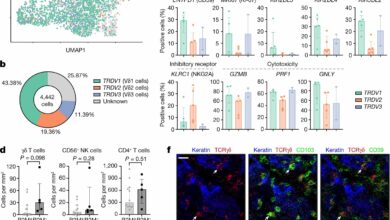

Células imunológicas especializadas carregam potencial para novas imunoterapias contra o câncer

Os subconjuntos de células T infiltrantes de tumor Vδ1 e Vδ3 exibem marcas de atividade citotóxica em cânceres de cólon…